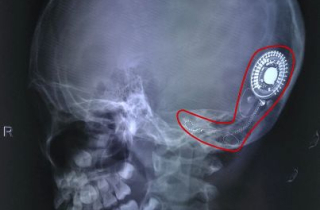

Thanh âm đầu đời của cô bé nghèo 7 năm sống trong thinh lặng

Lần đầu tiên nghe được tiếng nói nhờ cấy điện ốc tai, cô bé ở Đồng Nai mất vài giây ngơ ngác lặng người rồi...